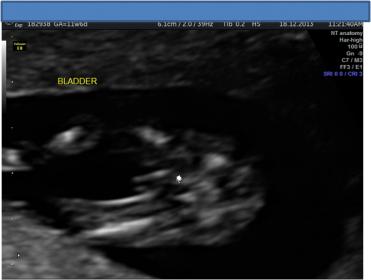

I know that potty shots are not accurate at this stage, however bub was not cooperative, and was upside down for most of the scan we really didn't get a good look at the nub. I have posted two shots, one is a potty shot and shows what looks like a very forked nub which is also what i saw in the ultrasound in the ultrasound however don't have an image of that particular shot of the baby. The second shot I am not even sure that is a nub as it is just not obvious to me - but posting it just in case.

Attachment 15762